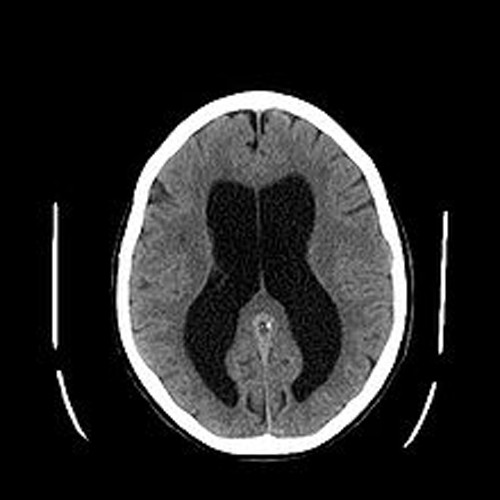

Vậy căn bệnh não úng thủy mà Quốc vương Thái Lan đang mắc là bệnh như thế nào? Não úng thủy xuất hiện do tình trạng dư thừa một loại chất lỏng trong não còn gọi là dịch não tủy (DNT). Sự dư thừa này dễ làm đầu bệnh nhân có dấu hiệu to dần, làm nhu mô não bị tổn thương.

Ở người lớn, não úng thủy ít có khả năng gây tăng kích thước đầu song nó có thể khiến các mạch máu da đầu giãn to hơn bình thường.

Não úng thủy gây tổn thương trực tiếp đến hệ thần kinh trung ương, thậm chí nó có thể để lại di chứng trầm trọng nếu không điều trị sớm và đúng cách.